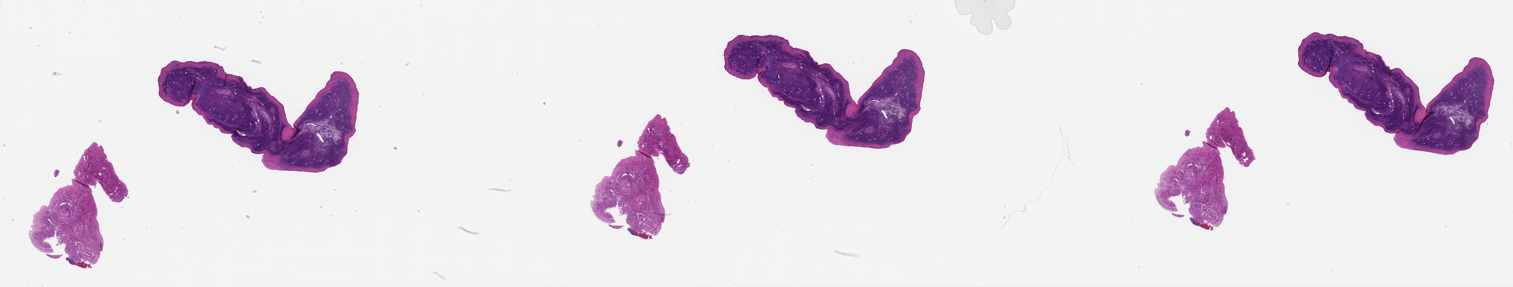

MDB0000493-38751_L_Ov_Baboon_20_yr_10_MZ_20128.tif2025-10-01 21:26 3.3G

MDB0000493-38751_L_Ov_Baboon_20_yr_10_MZ_20128_reduced.png2025-10-01 20:48 9.9M